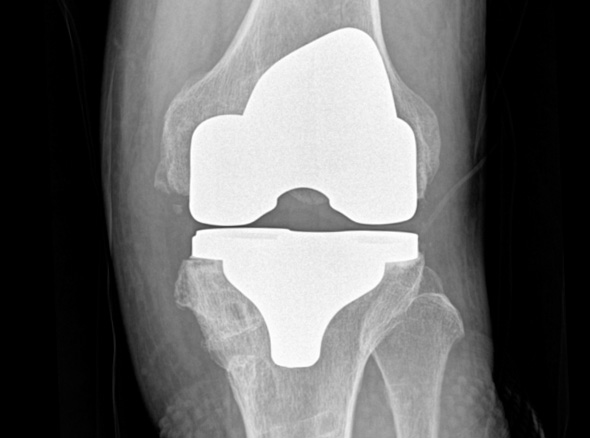

손상된 무릎 뼈를 제거하고, 그 부위에 특수 소재의 금속 재질로 구성된 인공관절을 삽입하는 수술을 시행할 수 있습니다.

관절연골이 망가져 쓸 수 없을 때 관절기능 회복을 위해 시행하며, 인공관절의 수명은 20~30년 정도 됩니다.

세계적인 의료기기 기업 스트라이커(Stryker)사의 특화된 임플란트를 사용합니다.

정밀한 설계, 내구성, 생체 적합성 등의 장점을 두루 갖추어 전 세계적으로 가장 많이 사용되고 있습니다.

최대한 가볍고 오래 사용 가능하며 알러지를 거의 유발하지 않는 인공관절을 사용합니다.